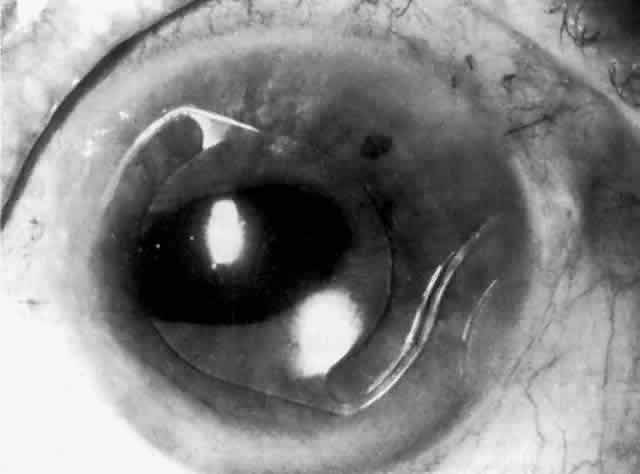

MANAGEMENT. The postoperative IOP elevation that occurs with the use of viscoelastic agents is exacerbated by cortical remnants and blood (Fig. 1). Careful cortical cleanup and aspiration of the viscoelastic agent may reduce the degree of IOP elevation. Prophylactic treatment of all patients (particularly those with preexistent glaucoma) with carbonic anhydrase inhibitors or beta-adrenergic blockers may decrease the incidence or severity of postoperative IOP elevation.35–38